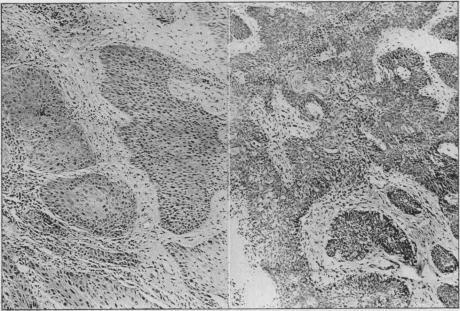

The analysis is of 55 cases admitted into St. Mark's Hospital from 1922 to 1940.The incidence was 3.35% of all cases of cancer of the rectum, anal canal and anus admitted during this period.Sex distribution-27 males and 28 females.The average age (61.7 years) is higher than that of columnar-cell carcinoma of the rectum (57.4 years).Histology.-The cases have been graded into three grades of malignancy-low grade, medium grade, and high grade.Low grade squamous carcinoma is twice as frequent in men as in women, and generally originates at the anal margin.Medium grade squamous carcinoma is equally distributed between men and women; it may arise at the anus or in the anal canal.High grade squamous carcinoma is much more common in the female sex and is almost entirely limited to the anal canal.Quadrant affected-about one-third of the anal margin growths and one-half of the anal canal growths were situated anteriorly.Differential diagnosis from simple papilloma, simple ulcer, chronic inflammation, tuberculous ulcer, tuberculide, primary chancre, amoebic ulcer, basal-cell carcinoma, columnar-cell carcinoma.Biopsy and grading essential before treatment is decided upon.The results of treatment in the three grades of malignancy are described. The best results were obtained in the early low-grade cases treated by interstitial radium needling. In the medium and high grades only three five-year survivals can be reported and these followed excision of the rectum. The management of the inguinal glands is discussed and the importance of a very close post-operative supervision emphasized.Squamous carcinoma of the anal canal may cause lymphatic metastases in the superior haemorrhoidal glands; there have been four such cases in this series. Diathermy perineal excision is indicated in these cases.